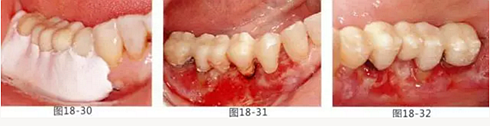

圖18-30 在頰側以及舌側涂上牙周塞治劑。然后將咬合面少許削除。

圖18-31 手術完成1周的頰側面照。

圖18-32 同部位的舌側面照。